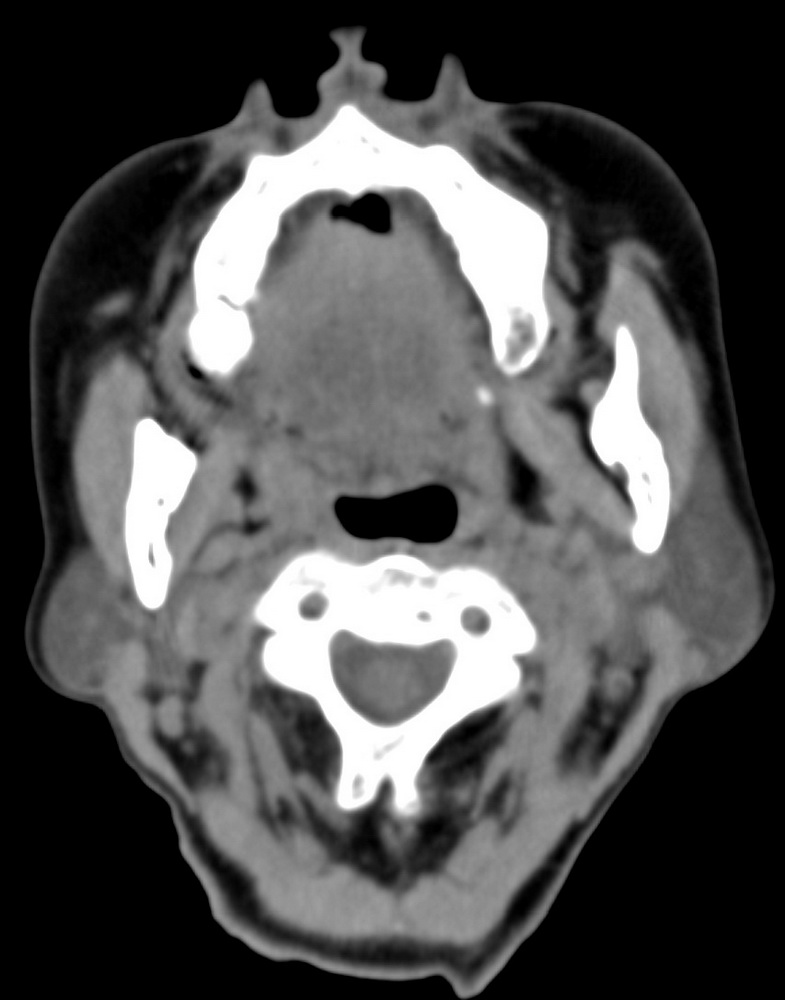

女,68岁。发现上唇无痛性肿块2年多,查体局部皮肤隆起,其余未见异常。

病灶ct值约42hu。

病理结果:唾液腺混合瘤。